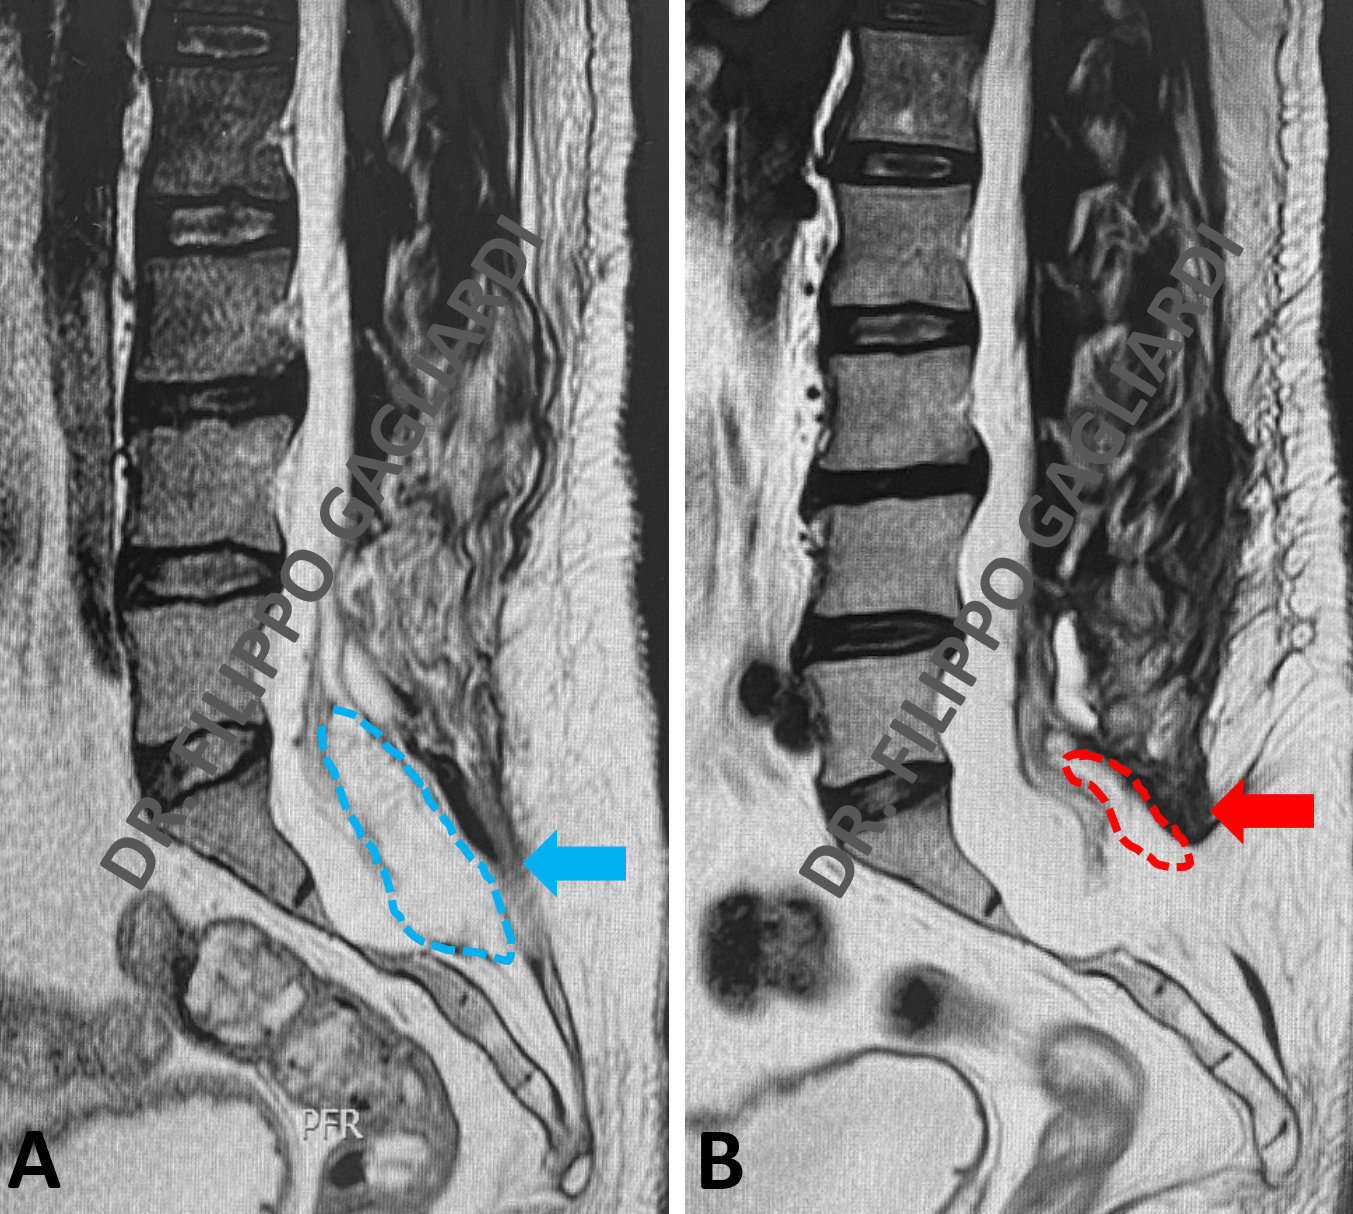

Patologia malformativa spinale Caso di paziente con tethered cord (midollo fissato) (midollo spinale fissato da un cordone fibroso a livello dell’osso sacro) associato ad un lipoma intradurale (tumore benigno di tessuto adiposo) a livello delle ultime radici spinali che presiedono al controllo degli sfinteri (freccia azzurra, Figura A).

È una condizione in cui il midollo spinale rimane ancorato verso il basso da un cordone fibroso (filum terminale) che lo stira verso il basso e ne causa sofferenza. In condizioni di normalità il midollo spinale termina a livello della prima vertebra lombare (cono midollare), nel caso presentato il midollo termina a livello della quinta vertebra lombare, perché stirato verso il basso. La paziente si presentava in ospedale per incapacità ad urinare (ritenzione urinaria) e perdita di feci (incontinenza). Veniva sottoposta ad intervento di disancoraggio midollare (sezione del cordone fibroso) e decompressione delle radici nervose mediante asportazione sub-totale del lipoma. L’intervento veniva eseguito sotto monitoraggio neurofisiologico per preservare la funzione dei nervi. La RM post-operatoria (Figura B) dimostra gli esiti dell’intervento con riduzione significativa del lipoma e detensione dei nevi e del midollo spinale (freccia rossa, Figura B). Nel post-operatorio si è assistito ad un miglioramento della funzione sfinterica della paziente.